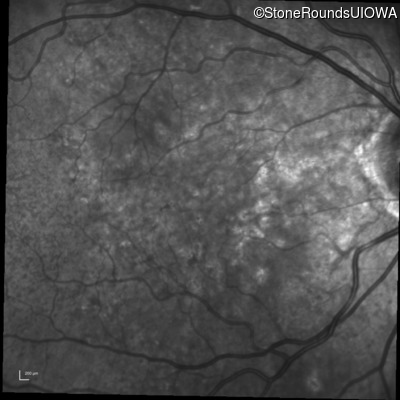

Infrared Fundus Photograph - Right - 20/20 -3 sc

Exemplar

Infrared Fundus Photograph - Left - 20/30 -2 sc